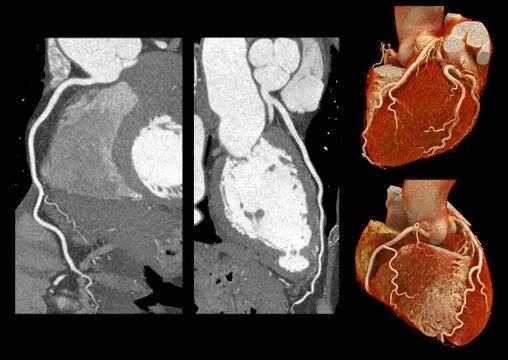

🔹在心血管成像中,CZT-PCCT通过更高的空间分辨率与更薄层厚成像能力,使血管细节及远端分支结构获得更清晰、连续的显示。对于小血管及复杂病变的观察,有助于提升影像评估的精细度,为心血管疾病的诊断与分析提供更加可靠的依据。